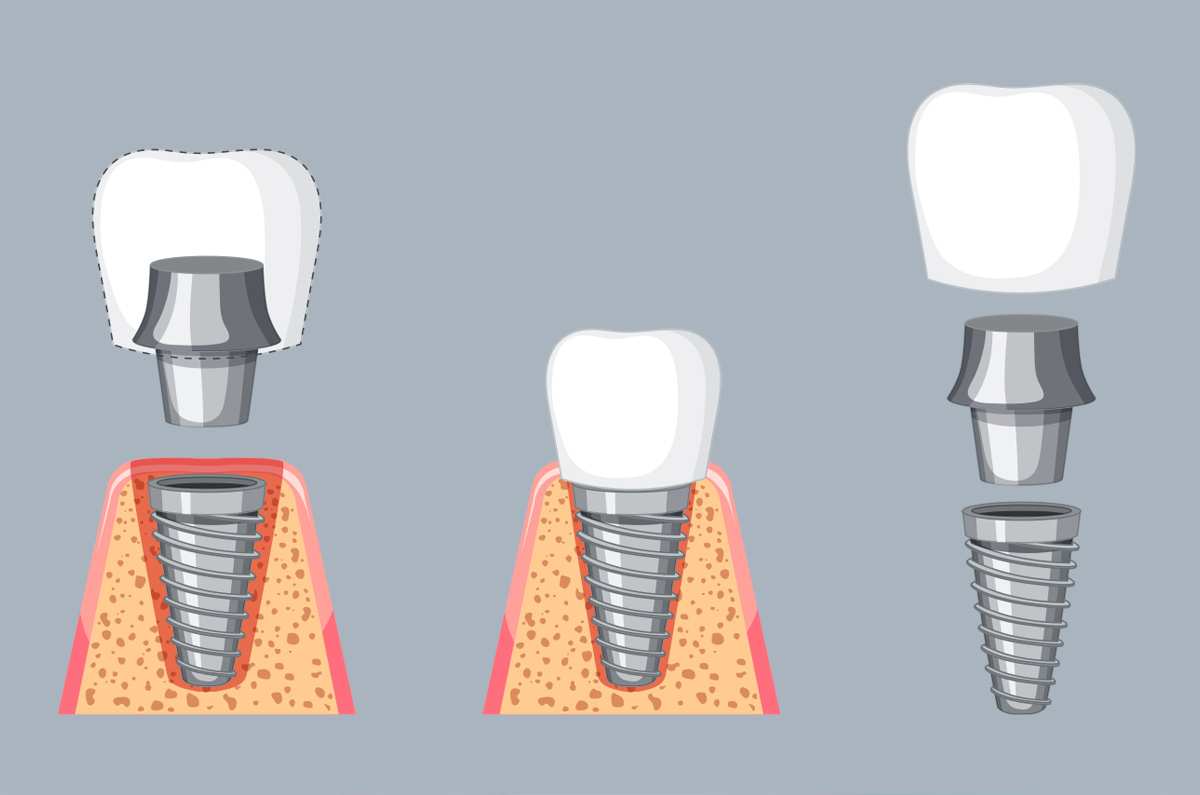

Amor Dental by Dr. Lorna M. Quimco offers premier dental services at affordable rates, including veneers, bridges, whitening, implants, TMJ therapy, braces, and dentures. Established in 1999, our goal is to provide top-notch dental care for confident smiles. Dr. Quimco, with over 25 years of experience, is renowned for her expertise in cosmetic dentistry. She graduated from Cebu Doctors University and pursued postgraduate studies at the Philippine Academy of Esthetic Dentistry, excelling in Dental Implantology under Dr. Hom-Lay Wang at the University of Michigan.

She practices Biomimetic Dentistry, focusing on preserving tooth structure by replicating natural tissues. She also specializes in Neuro-Muscular Dentistry, employing advanced techniques for personalized treatment plans. Committed to continuous learning, she travels globally for the latest innovations.